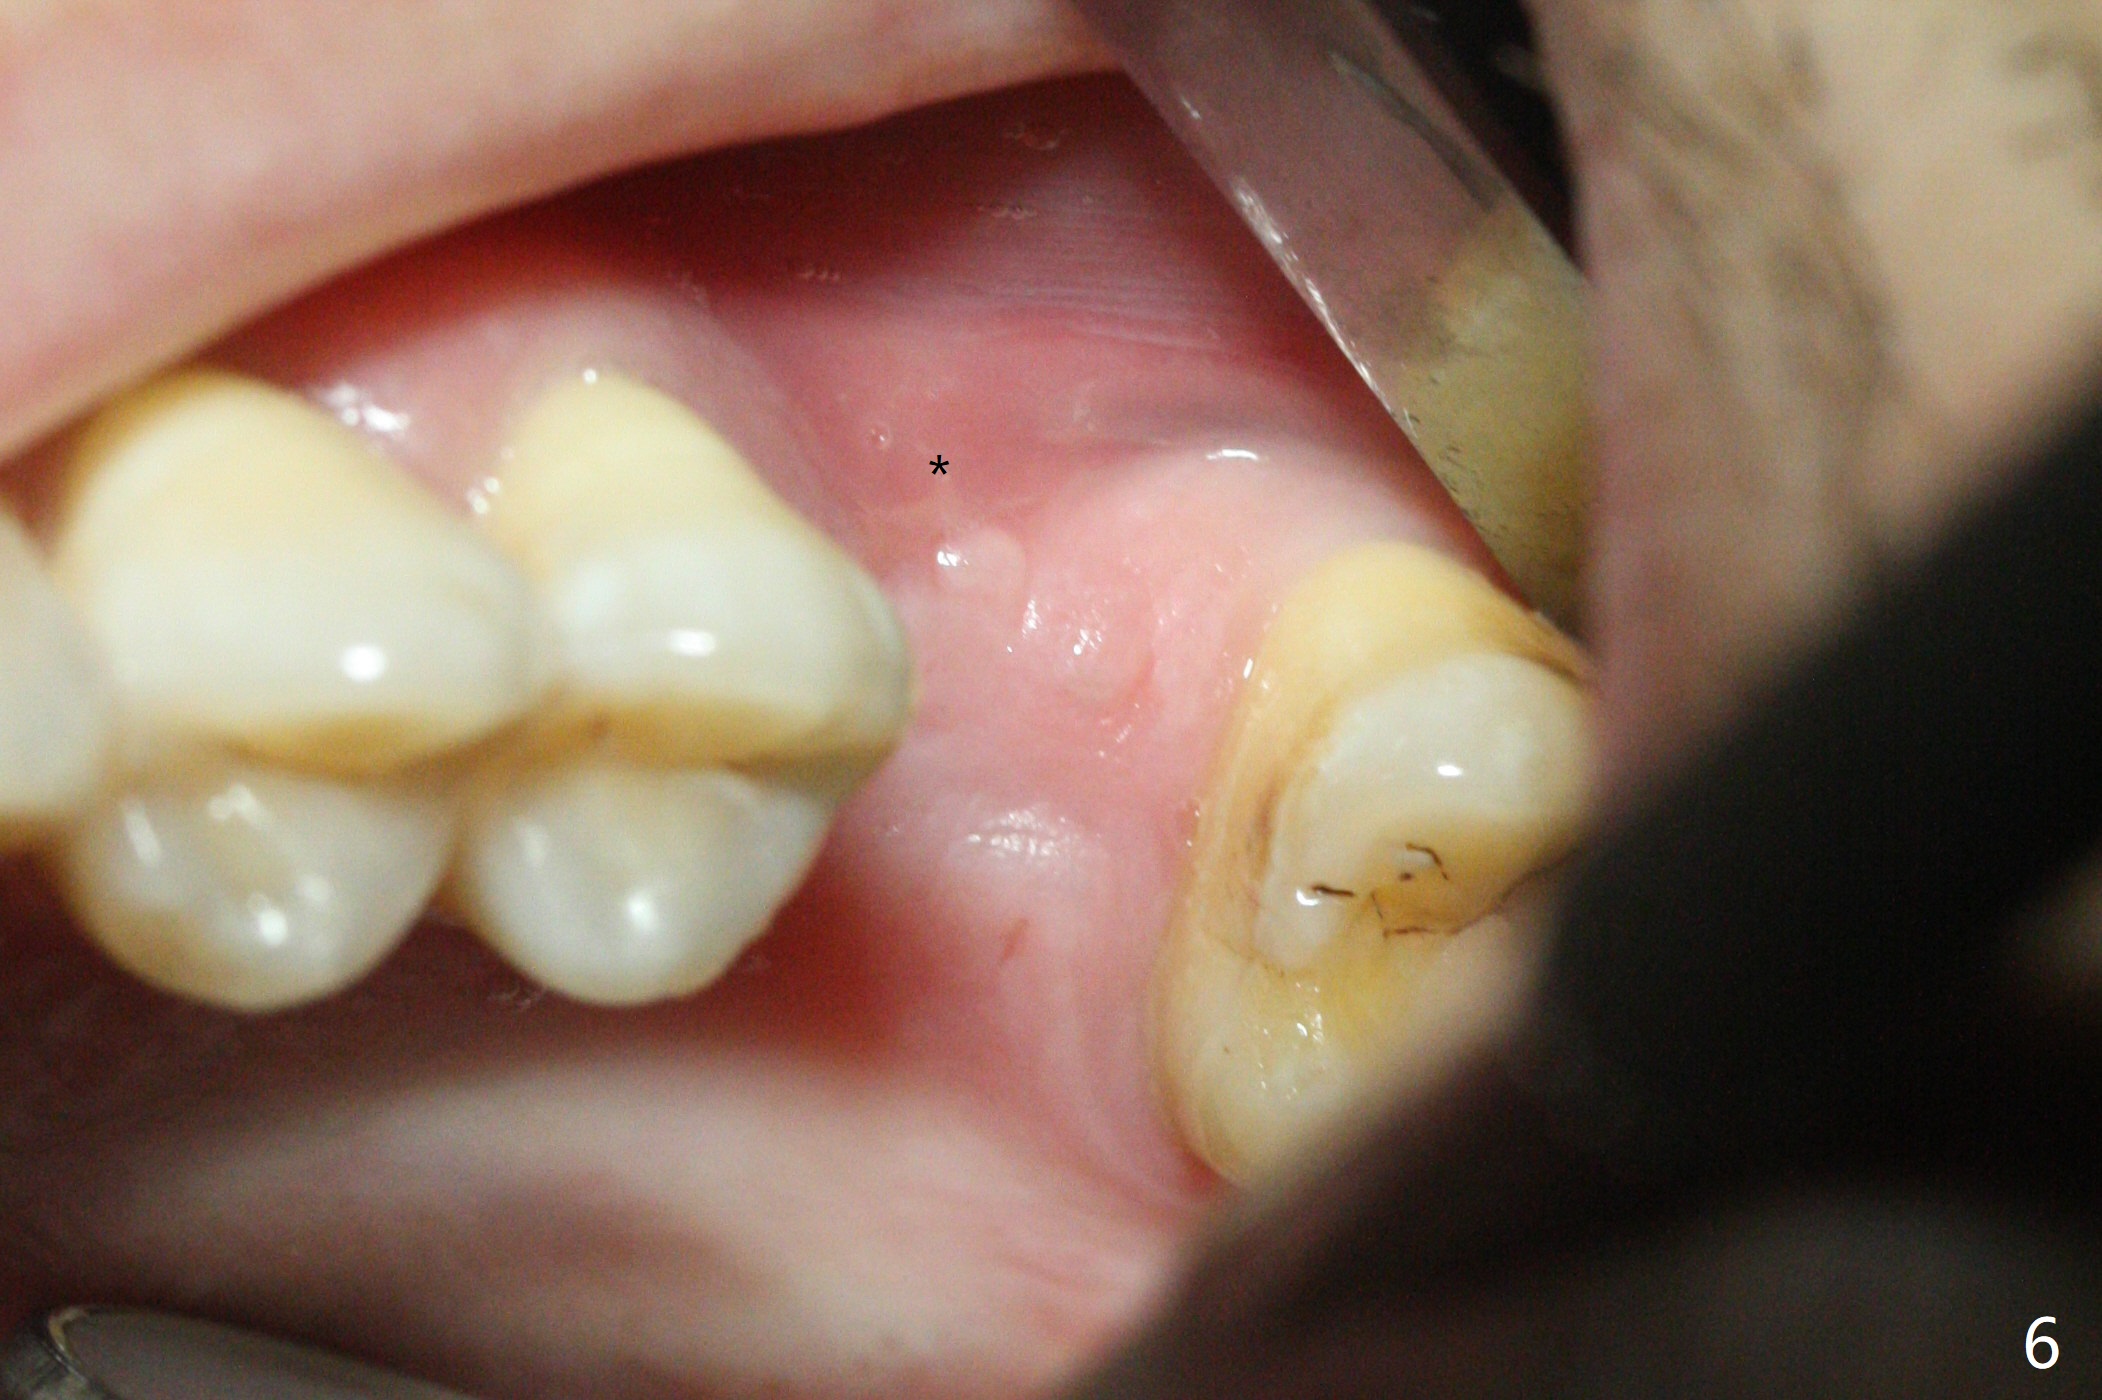

When the crown and abutment at #14 are removed, the implant is found to be shallowly placed. Upon incision, the implant threads are exposed circumferentially and coronal to the buccal crest (Fig.1 *). It seems to be difficult to expect bone regeneration post bone graft. The implant (6.4x6 mm) is removed with a 7/8 mm trephine bur, followed by sticky allograft (Fig.2 *), PRF membrane and 6-month membrane. In spite of the setback, the bone height increases from 3.9 mm to 11 mm due to sinus lift associated with the previous implant placement (Fig.2 L). The depth of the 2nd placement will be controlled by surgical guide. When the periodontal dressing dislodges 11 days postop, the 6-month membrane is lost as well as part of the bone graft. If there is remaining apical native bone, an immediate implant should be placed so that bone graft can be kept in place more securely with an immediate abutment and provisional! The seemingly conservative approach is actually not safe. The wound heals 1 month postop (following dislodgement of the 2nd periodontal dressing, Fig.3). Three months later, consider using bone expanders to do sinus lift and place a SM implant subcrestal. Take PA after 1st expander to the depth. The wound heals 4 months postop (Fig.4), but the bone height (Fig.5) and width (Fig.6) decreases. The latter continues to decrease 9 months postop (Fig.7,8), but bone density is high, average 1360 units. Preparation includes guide, incision, sinus lift, implant placement (possibly tissue-level (9) or FC if the sinus membrane perforates), bone graft, and suture.